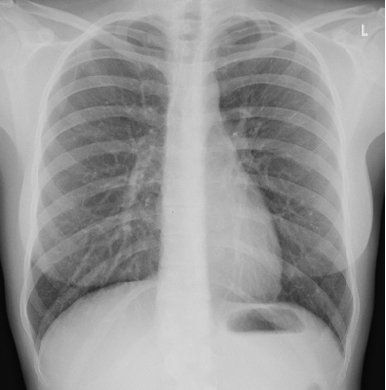

0: Lungenröntgen p.a.

thoraxu _1_.jpg

Download Photo (420 x 390)

Datum: 09.09.2009

Betrachtungen: 46